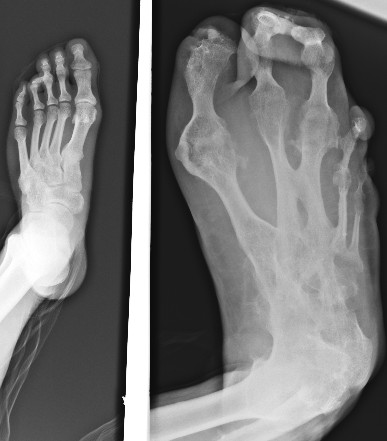

男性,35岁,左足随年龄增大,无疼痛及其它不适。还能开车了。

幼年时就大吗,如果是就是先天性畸形--巨足症。

考虑为:左足遗传性多发性骨软骨瘤并血管瘤(动脉瘤?)。

考虑先天性巨肢症(节段性肥大)。

支持!另外还有诸关节间的骨性强直。

左足个组成骨部分融合,形态失常(患者未感异常)

考虑先天病变(节段性肥大)

(左足随年龄增大,无疼痛及其它不适)考虑为多发性 内 外生骨软骨瘤。

巨足畸形合并并趾畸形。

巨趾畸形。遗传?或并发血管瘤或神经纤维瘤

符合先天性巨肢症,临床资料需完善。1\2\3跖趾骨肥大为主要表现,但骨关节形态有些失常,有部分融合,是否曾有过感染。